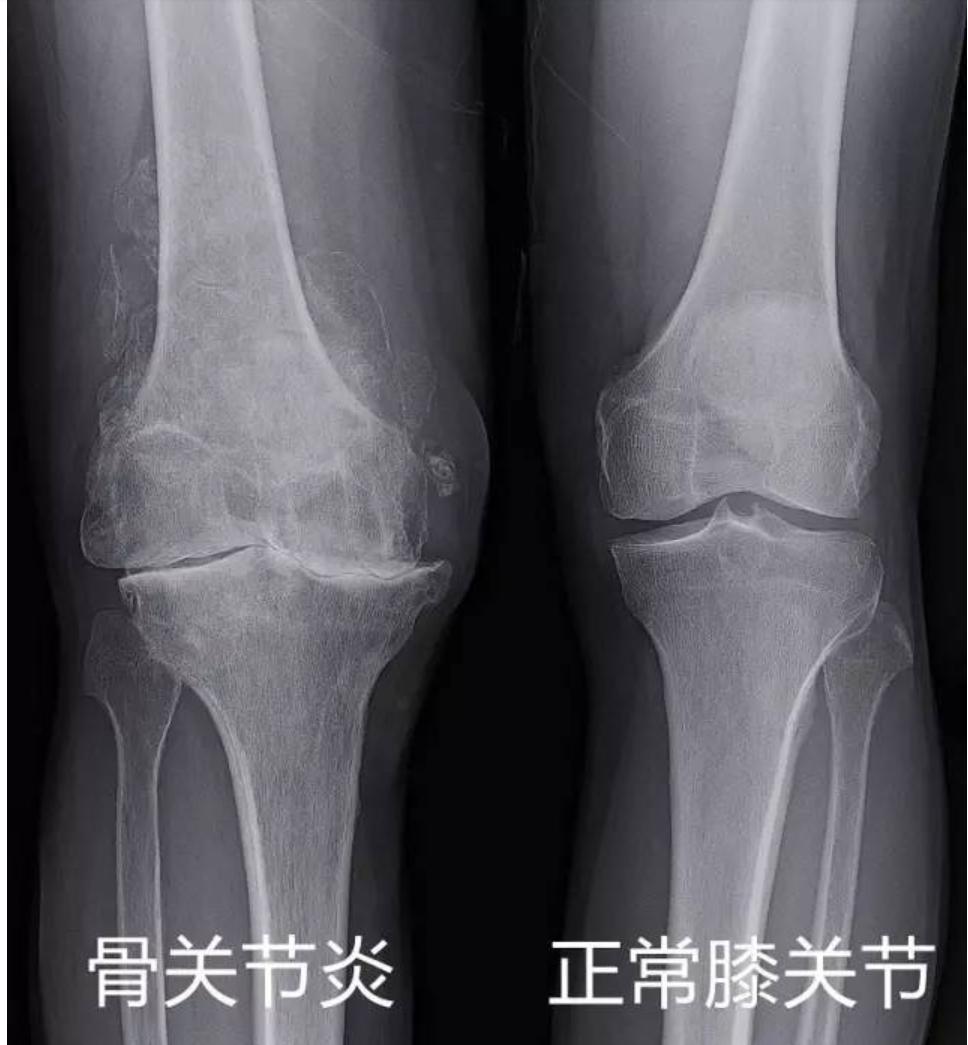

很多中老年人因膝关节疼痛到医院拍片后大都被告知"关节内长骨刺或者骨质增生"、"关节间隙变窄"了,久而久之"关节内长骨刺"就在普通百姓当中耳熟能详了,其实"关节内长骨刺"并不是一个疾病,只是X线拍片检查中所发现的一个病变而已。对于膝关节而言,准确的疾病名称是膝关节骨性关节炎。

膝关节骨性关节炎是以退行性病理改变为基础的疾患。是一种以关节软骨的变性、破坏及骨质增生为特征的慢性关节病。多患于中老年人群,其症状多表现为膝盖红肿痛、上下楼梯痛、坐起立行时膝部酸痛不适等。也会有患者表现肿胀、弹响、积液等,如不及时治疗,则会引起关节畸形,残废。